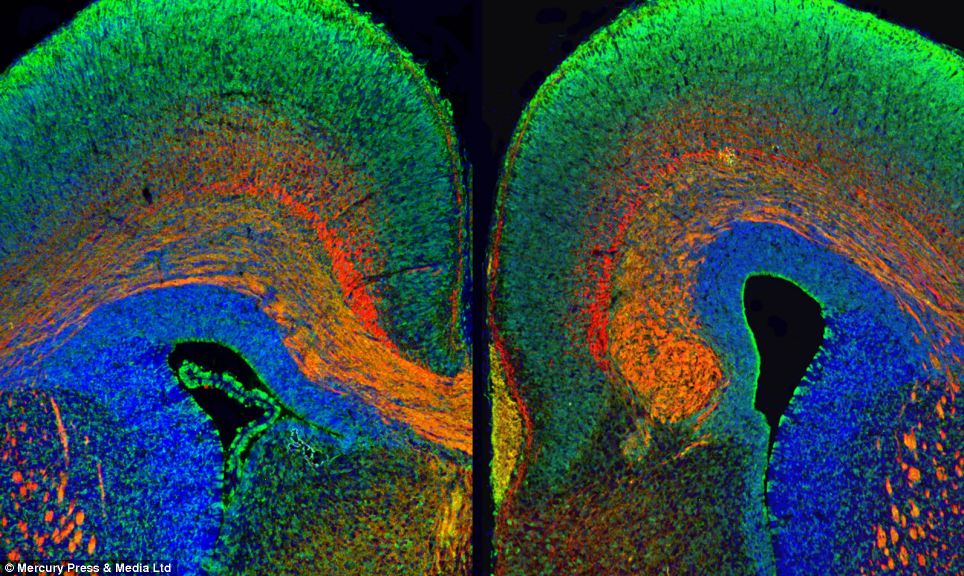

Kështu kanë menduar specialistët e mjekësisë në St Andrew Square në Edinburgh prandaj kanë treguar pamjen e trurit nëpërmjet një kaleidoskopi.

Nëpërmjet këtyre imazheve mund të bëhet dallimi midis trurit të një njeriu të ri dhe të vjetër, midis trurit të një mashkulli dhe femre, dallimi midis një truri tipik dhe truri autik.

Imazhet paraqesin shumë ngjyra dhe janë bërë të mundura duke përdorur skanimet MRI, imazhet mikroskopike dhe monitorimin energjitik.

Në foto mund të dallohen madje edhe qelizat në aksion.

Sophie Dow shprehet se është fatale që këto imazhe të mrekullueshme të mbeten vetëm brenda një laboratori.